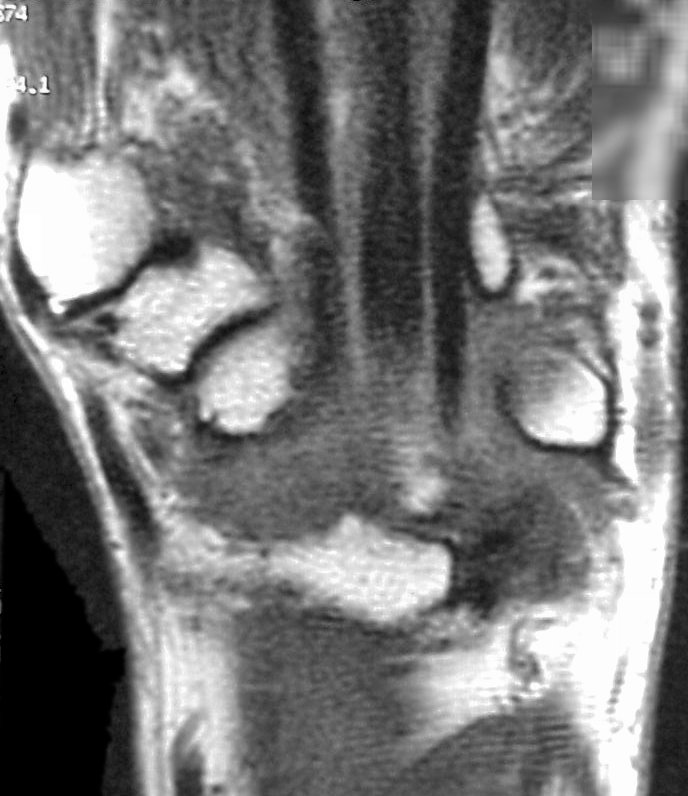

Mild wrist stiffness prevented adequate visualization of the hook of the hamate with plain films. Plain films of the finger were normal for age. Further evaluation was obtained with MRI. Flexor tendon signals in the finger were normal:

Sections through the carpal tunnel -  looking for a hook of hamate fracture or tendon discontinuity - were read as normal, although there may be a subtle signal irregularity through the hook of the hamate: